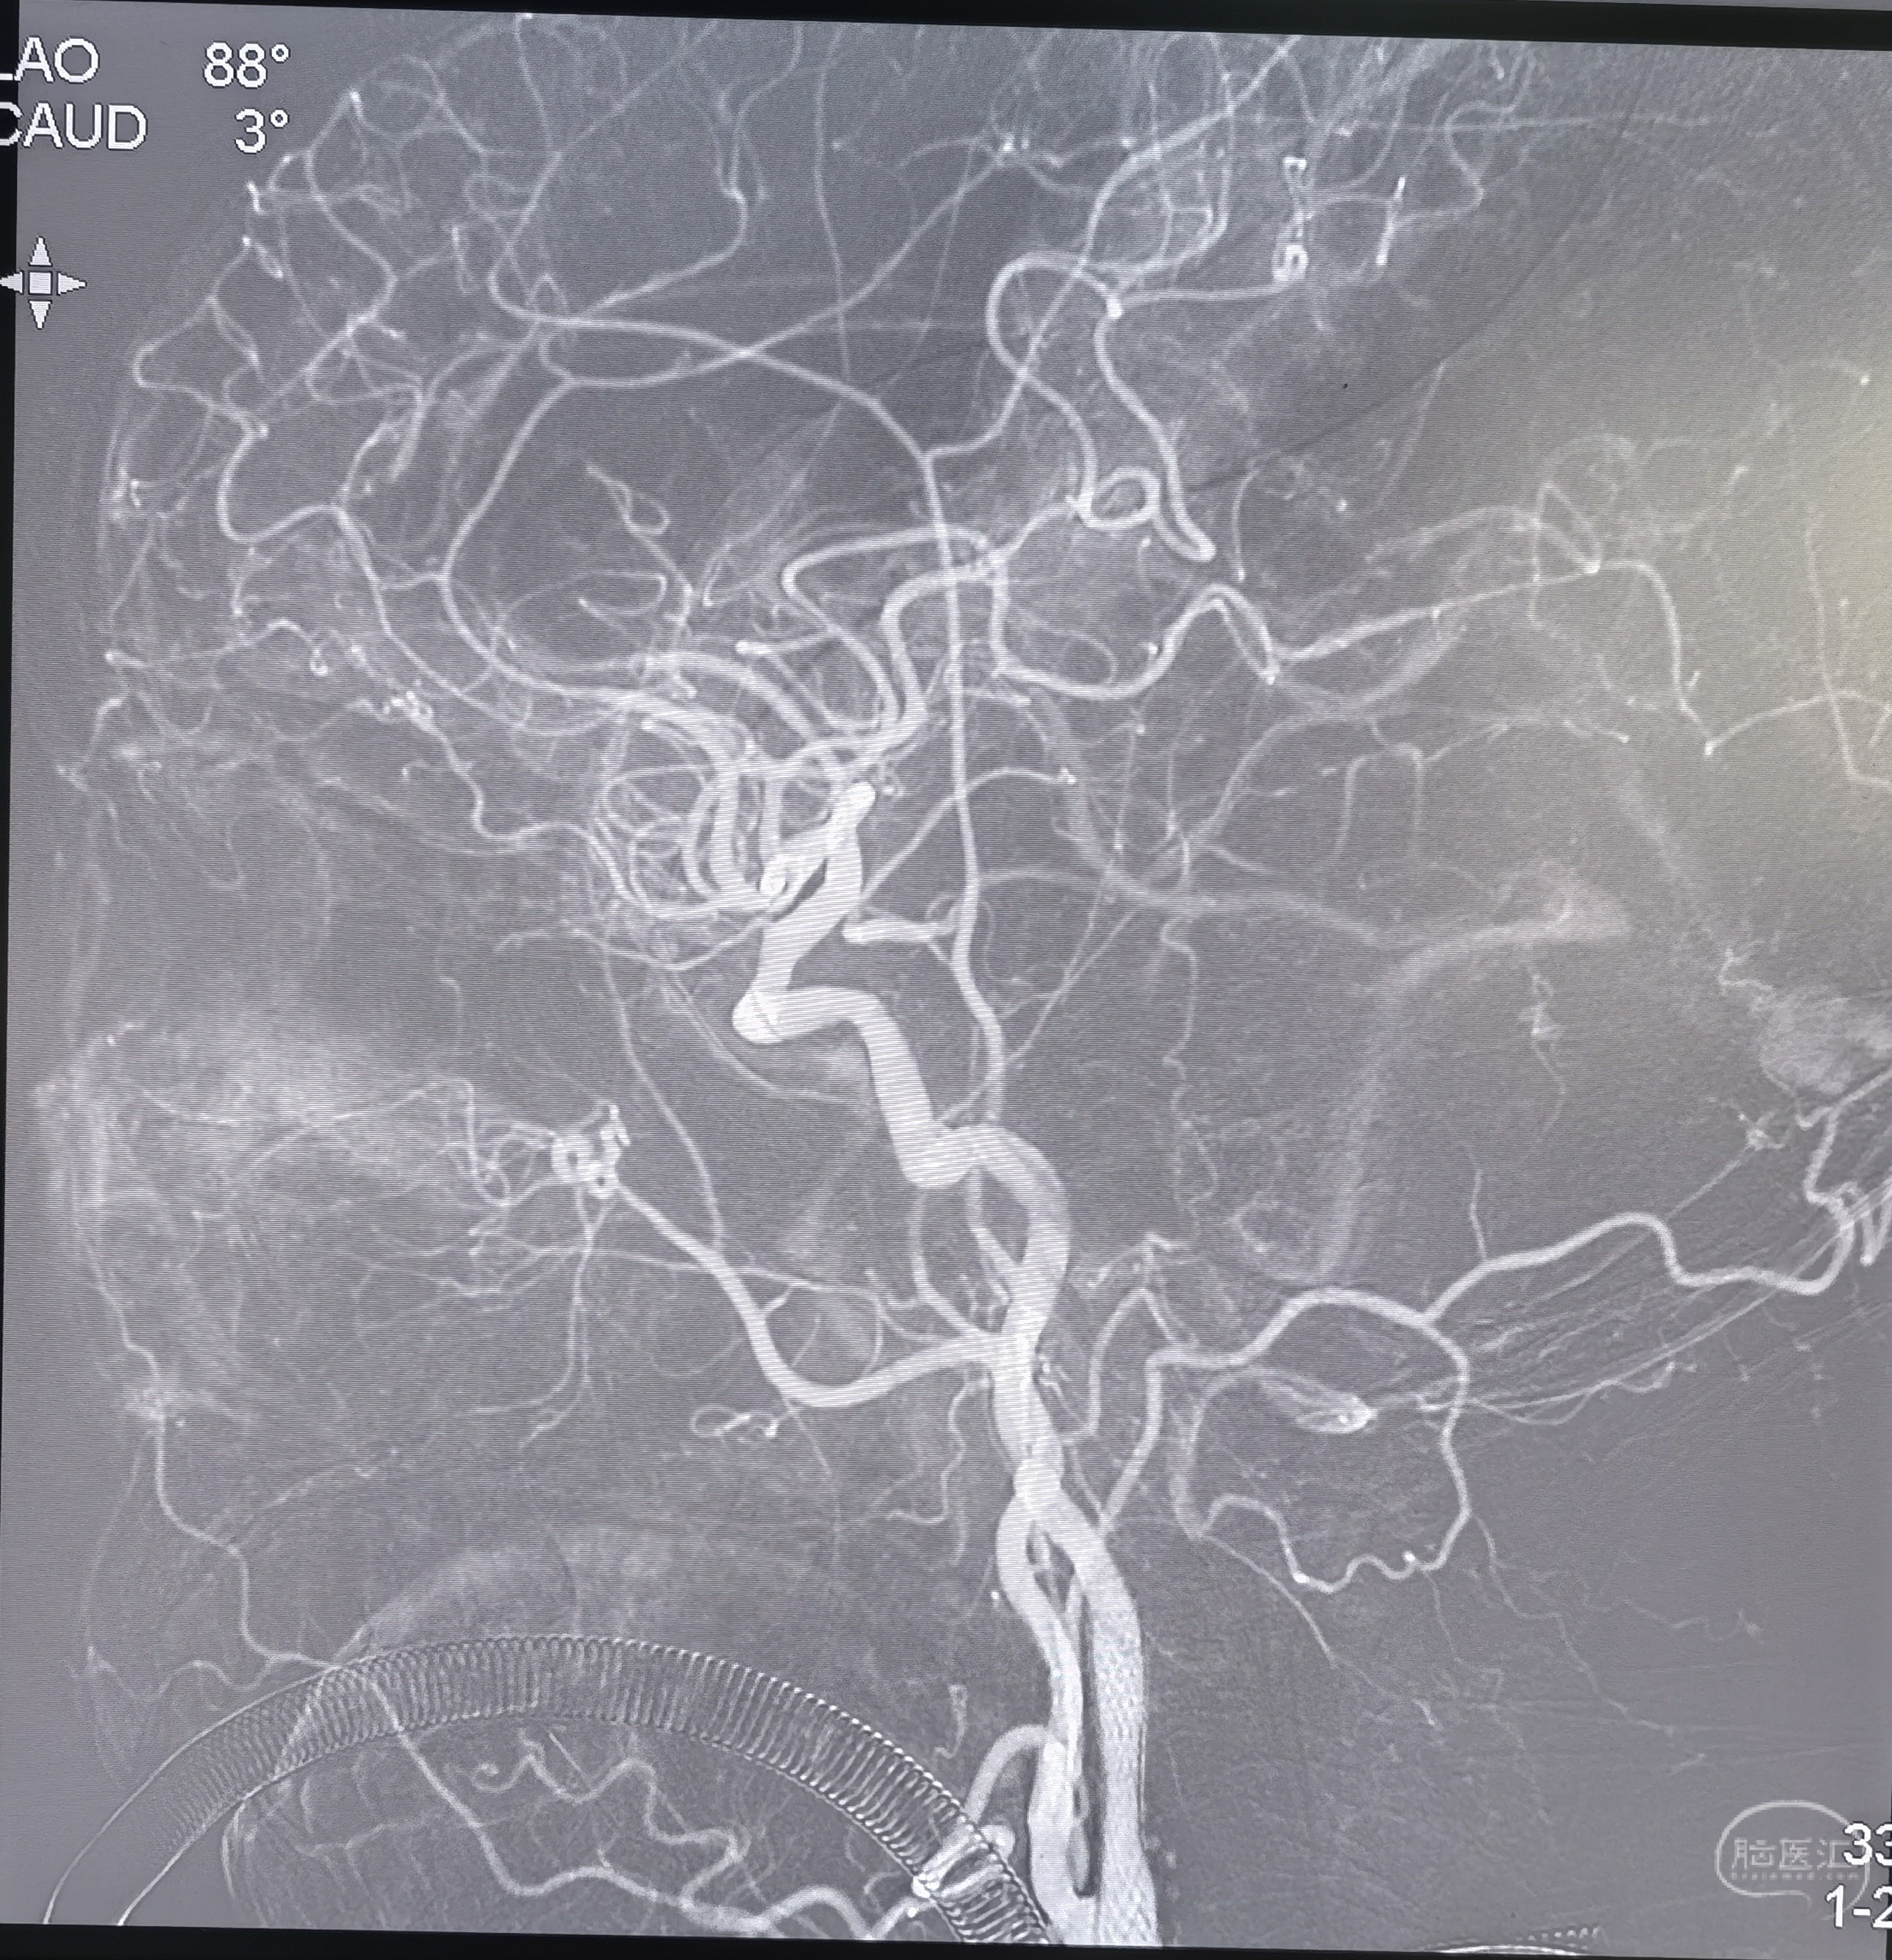

支架置入后造影正位